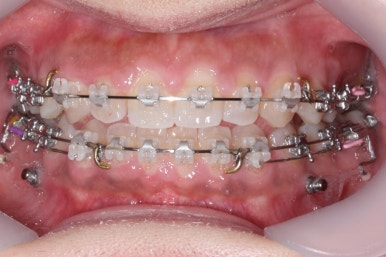

전후를 비교해 보겠습니다.

부산치아교정치과 전후 모습입니다.

변화가 놀랍습니다.

얼굴 모습에도 많은 변화가 있었습니다.

턱에 대한 교정치료를 하지 않았지만 옆라인이 훨씬 좋아졌습니다.

뒤집어진 U자 형태의 입술꼬리도 개선되었습니다. 아마도 교정치료 후의 자신감 증대가 큰 원인이지 싶습니다.

웃는 모습이 다른 사람인듯 좋아졌습니다. 웃을 때의 입의 크기 부터 보이는 치아의 가지런함까지 매우 좋아졌습니다.